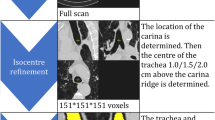

A MRI body phantom (Fig. E1), with four bottles filled with potassium sorbate (General Electric Healthcare), was used to assess the effect of GD on volume quantification depending on six different scan settings: (1) reference position with phantom centered in the scanner isocenter, (2) electronic displacement of FOV to simulate incorrect FOV positioning by a MRI technician, (3) manual displacement of phantom to simulate possible patient’s movements in the scanner, (4) table repositioning to simulate whole-body MRI protocol, (5) parallel imaging with different acceleration factors for faster image acquisition, and (6) use of torso coil to replicate the lung MRI protocol of the prospective population-based Generation R cohort study. For settings (2) and (3), eight different phantom positions distanced 5 cm from the isocenter were tested: left (L), right (R), inferior (I), superior (S), left inferior (LI), right inferior (RI), left superior (LS), and right superior (RS). For setting (5), four different acceleration factors were tested (1, 2.25, 4, 5). For setting (6), three positions were tested: torso coil centered on the subject and torso coil distanced 5 cm left or right from the center. All images, except setting (6), were acquired with body coil to obtain the most homogenous signal from the phantom and thus facilitating volume segmentation. Images were collected with in-plane bidimensional (2D Gradwarp) and full three-dimensional (3D Gradwarp) GD correction. These correction techniques correct spatial distortion artifacts and blurring at the extreme margins of MR images determined by only nongradient field nonlinearity [20].

Subjects’ data

To test lung volume segmentation methods, lung MRI data of a subset of 11 anonymized children were randomly selected from the Generation R Study [21, 22]. After written informed consent (METC-2012-165), children underwent whole-body MRI, including brain, heart, hips, and lung MRI acquisitions. The MRI scans were carried out in a specially designed child-friendly MRI research facility. From November 2014 to January 2016, 5000 MRI scans were acquired in the Generation R Study. Each subject underwent two end-inspiratory and two end-expiratory spirometer-guided MRI acquisitions. Data were acquired with 2D and 3D Gradwarp. In particular, 3D Gradwarp of the scanner was applied to one end-inspiratory and one end-expiratory scan (Fig. 1).

Flowchart of acquisition scheme per subject. Each subject (n = 11) underwent two end-inspiratory and two end-expiratory acquisitions. 2D and 3D Gradwarp correction was applied to one end-inspiratory and one end-expiratory scan. In total, 11 subjects underwent four acquisitions, resulting in 44 scans